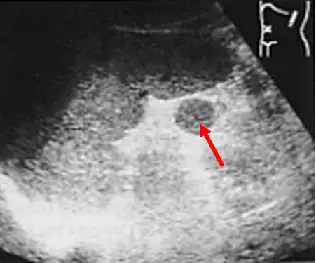

脾臟超音波掃描如附圖影像,箭號所指最可能為何?

- 主要結構:影像中顯示一扇形超音波掃描(呈現為腹部左上四分體),可見一大片實質、回音均勻的中等回音(Medium echogenicity)器官,即為脾臟(Spleen)。

- 箭號所指病灶:在脾臟周圍(通常位於脾門處 splenic hilum),箭號指著一個邊界清晰、呈現圓形或卵圓形的實質結節(Solid nodule)。

- 回音特性(Echogenicity):此結節的內部回音與一旁正常的脾臟實質完全一致(等回音,Isoechoic),且具有相同的質地(Homogeneous echotexture)。這是副脾最核心的影像學特徵。

- (B) accessory spleen(副脾):正確。副脾是脾臟發育過程中的先天性變異,由未融合的脾臟組織形成。在超音波下,其典型表現為位於脾門附近、邊界清晰的圓形或橢圓形實質腫塊,且其回音強度與質地與周圍的主脾完全相同(Isoechoic)。

根據上述影像分析,圖中箭號所指的結構位於脾臟附近,呈現邊緣平滑的圓形,且最關鍵的特徵是其內部回音與脾臟實質完全相同(Isoechoic)。這符合副脾(Accessory spleen / Splenunculus)的典型超音波表現。副脾發生率約在 10-30%,最常出現在脾門處,通常為無症狀的偶然發現。在影像診斷上,確認其回音及血流動力學(若使用顯影劑或都卜勒)與主脾一致,是鑑別診斷的關鍵。因此正確答案為 (B)。